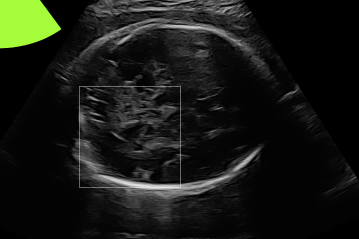

Three in vivo Bmode fetal images with and without aberration correction are presented in Figs. 10-12. GIF images of examples A-L (see Fig. 9 and Table 5) alternating between the corrected and uncorrected images are uploaded as supplementary material. The differences in image quality are easier to appreciate in the GIFs than in a side-by-side comparison. The data points for the three examples are colored black in Fig. 9. Table 5 give tabular values for the global sound speed estimate, sharpness increase (κ𝜅\kappa) and answers from the clinical evaluations.

Figure 10: Example A. In vivo fetal Bmode image using constant 1540 m/stimes1540dividemetersecond1540\text{\,}\mathrm{m}\text{/}\mathrm{s} and the estimated average sound speed map. The average sound speed map is shown in the top right corner and the rightmost colorbar indicates the sound speed values. Alternating GIFs are found in the supplementary material.

The in vivo examples A-C, in Figs. 10-12 respectively, show different nuances of how sound speed aberration correction improves focusing quality. A noticeable improvement in Fig. 10 is the improved contrast and clarity of borders. The sound speed correction seems to remove the double structure indicated by the arrows in Figs. 10c-10d. The skull border and the brain structures in Fig. 11 are also better defined and clearer after aberration correction. Example C in Fig. 12 is the image with the highest increase in Tenengrad κ𝜅\kappa, seen from Fig. 9 and Table 5. The improvement in image quality is evident around the boundary of the fetus body and the correction sharpens the structures indicated by the arrows. The improved contrast between the layers in the shallow tissue layers is also noticeable.